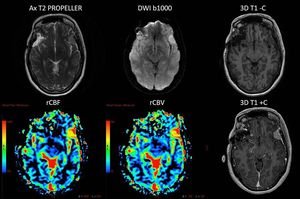

Multiparametric MR Imaging of brain's meningioma, based on high-resolution morphological (axial T2 PROPELLER and IR-prepared 3D T1 GRE pre and post contrast are shown here) and functional (DWI b1000 and DSC PWI are shown here, also DCE PWI was acquired) acquisitions. The high rCBV and rCBF of the lesion should be noted.